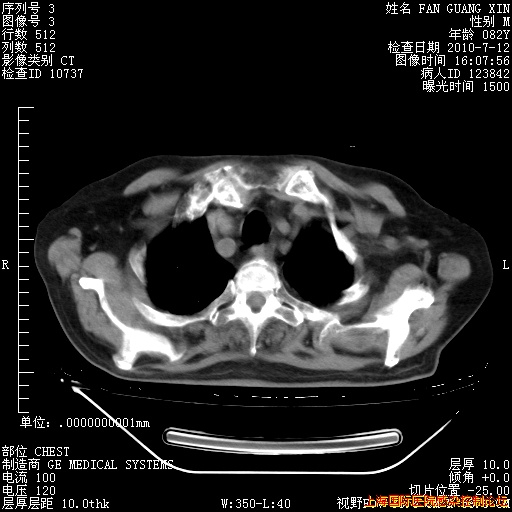

6月12日纵膈窗

今天CT

整整相隔30天的肺部CT好像有所好转啊。甲强龙减量第3天,需要观察体温。

海管,自昨日你和我通完话后,不知您岳父消化道症状有无缓解?体温怎样?阅读7.12日胸部ct,个人认为目前激素治疗是有效的,甲强龙减量是适宜的。因在抗痨治疗,需密切观察肝功、肾功能和血常规。不过,老年、长期住院和大量使用激素,很担心菌群失调发生